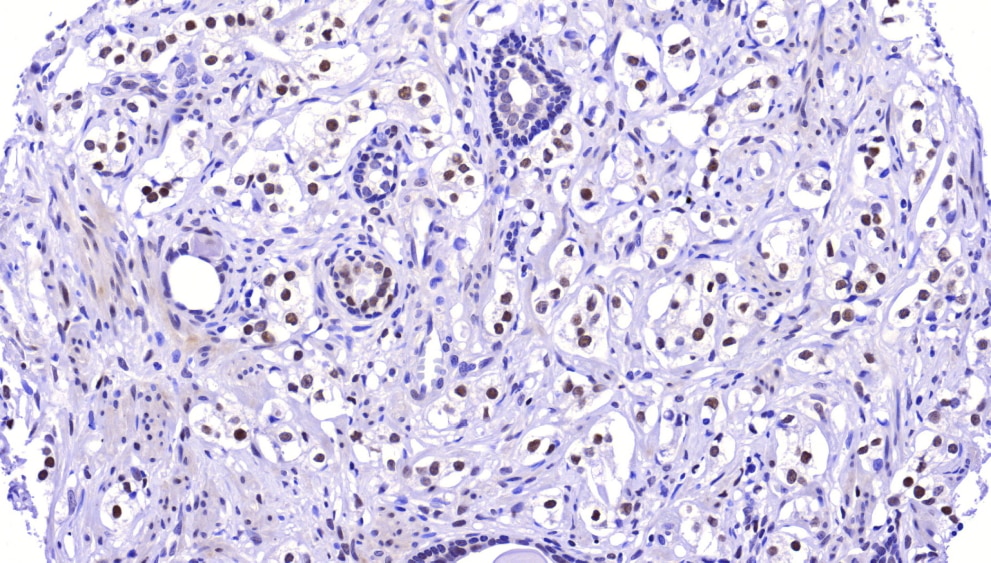

Immunohistochemistry-Paraffin: Dnmt3L Antibody [NBP2-39076] - Prostate cancer tissue stained with DNMT3L. Intense nuclear staining in carcinoma cells. (original magnification X200). Image submitted by a verified ...read more

For IHC-Paraffin, HIER pH 6 retrieval is recommended. Dnmt3L antibody validated for IHC-P from a verified customer review.